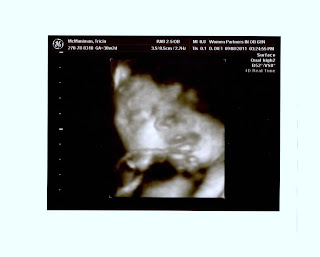

This is one of the 4D-type pictures we received.  You cannot see part of CG's head

becuse it is so low.  However, you can see his/her closed right eye, nose, mouth,

and right hand, which  is just under his/her mouth. (This is a head-on view.)

I made another appearance at the doctor's office today, but unlike the previous visits, this appointment was scheduled.  The doctor requested an ultrasound to check my amniotic fluid, which measured really well.  At 30 weeks the amniotic fluid should be above 9 cm and below 26 cm;  my fluid measured at 16 cm.  In addition, the technician measured the weight of the baby.  CG weighed in at 3.5 pounds, which is a little above the normal weight at this gestational age!  Sean and I were also able to see a 4D-type view of CG.  CG was not too active during this viewing, but he/she smiled for us twice.  This was definitely an exciting moment for Sean and me.  The doctors can no longer predict what is going to happen. (Actually, I think they gave up awhile ago!)  So, right now it is somewhat of a waiting game, which we hope lasts at least a few more weeks.